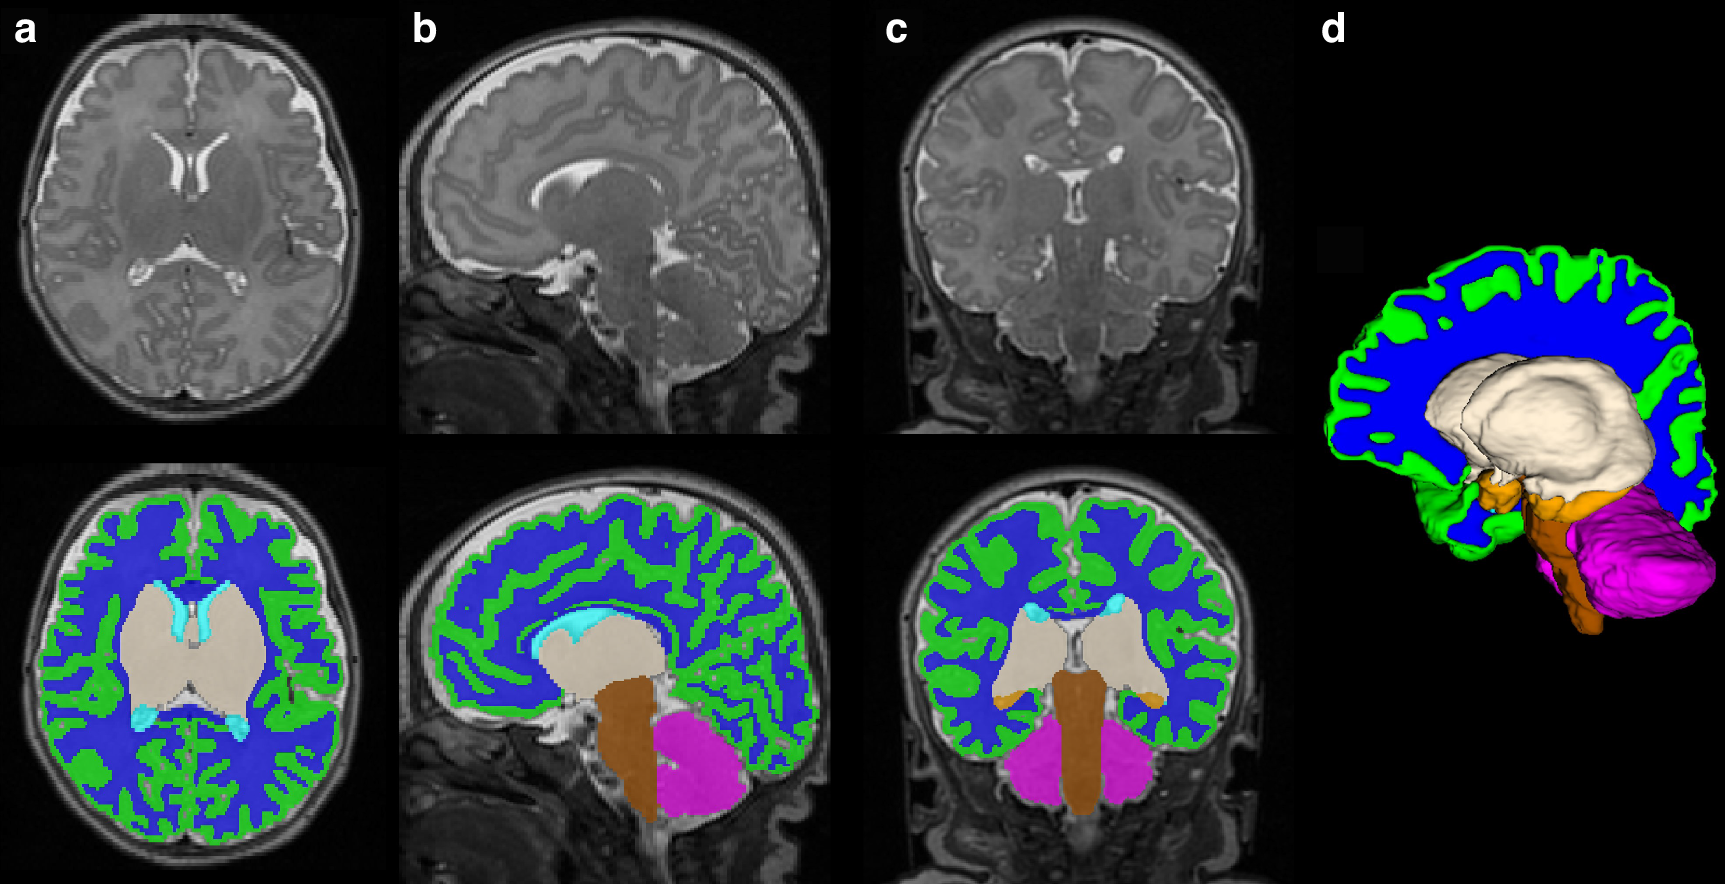

Fig. 1: Term equivalent volumetric segmentation images.

From: Donor human milk and structural brain development in very preterm infants

T2 brain MRI images with corresponding volumetric segmentation in the a axial, b sagittal, and c coronal planes with d 3D volumetric reconstruction. Green: cortical gray matter, blue: white matter, gray: deep gray matter, tan: amygdala-hippocampus, pink: cerebellum, brown: brainstem.